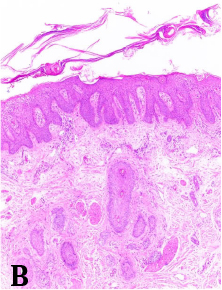

Haga usted el diagnóstico. Parte 1

Haga usted el diagnóstico. Parte 2